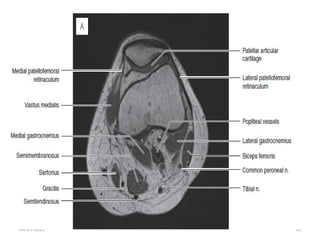

Tibial Nerve

• Largest division of sciatic nerve.

• Arises from ventral surface of sacral plexus(L4-S3) and runs

medially.

• Courses through the popliteal fossa passing deep to

gastrocnemius muscle.

04/29/2025 22

• It passes inferiorly between the heads of gastrocnemius and

deep to soleus muscle.

• Continues inferiorly in the midline deep to soleus and

superficial to the tibialis posterior muscle.

• At the ankle passes under flexor retinaculum in the tarsal

tunnel.